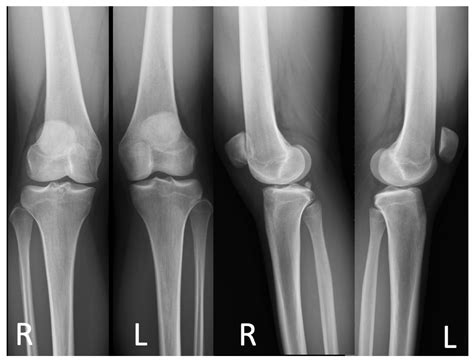

Diagnosing subluxation typically involves a combination of physical examination and imaging tests. A healthcare provider will perform a thorough evaluation to assess the spine's alignment and function. This may include:

• Imaging Tests: X-rays, MRI, or CT scans may be used to visualize the spine and identify any misalignments or abnormalities.